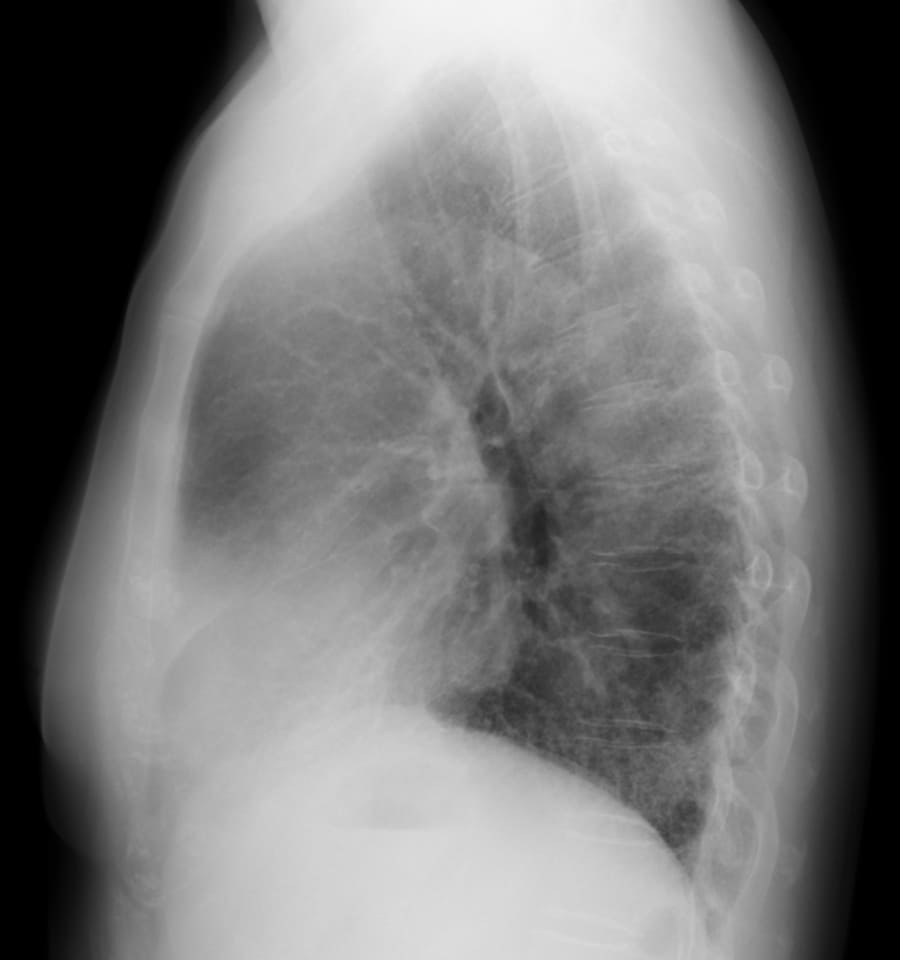

DATA 1| X 線検査結果

画像にマウスオン(またはタップ)すると虫眼鏡で拡大できます

できます

気管支血管束に沿う均質な網状変化と重なるすりガラス影。

一部、胸膜下をスペア。fNSIP+UIP混在。

肺動脈は太めで食道の拡張あり、膠原病肺の疑い。